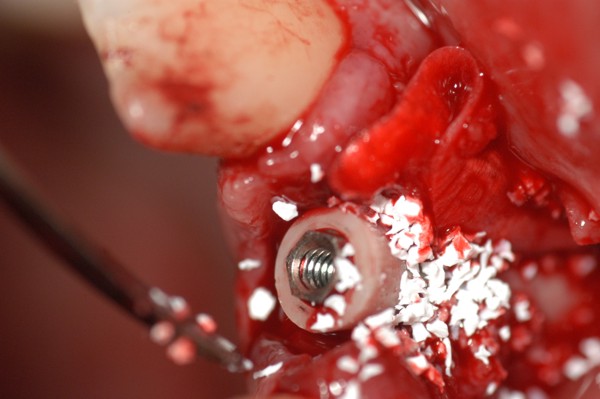

Abstract: Las fuerzas anterógradas traumáticas son en general las causantes de fracturas radiculares en el sector anterior de la boca. Desarrollo: El paciente se presenta a la consulta , con la fractura de una funda de porcelana inyectada en la zona cérvico palatina, solicitando simplemente la reparación en boca para evitar rozamientos linguales. Dicha funda con un perno colado en oro y su correspondiente endodoncia, habían sido realizadas en mi clínica varios años atrás, con un «aparente éxito total». Radiograficamente, se encuentra una fractura radicular cercana al tercio gingival Observada la oclusión de las piezas anteriores, podemos ver que el vínculo ideal de Acoplamiento, no se cumple, habiendo una relación de franco contacto la que ha provocado la fractura. Llevando al paciente a Oclusión en Relación Céntrica, podemos ver el espacio a nivel anterior, correspondiente a la centricidad mandibular. En esa misma posición , es dable percibir una faceta parafuncional mesial del primer premolar superior… …que antagoniza con una faceta parafuncional distal del canino inferior… ..constituyendo un plano inclinado que provoca la antelación mandibular o Discrepancia Horizontal, fracturando la raiz del incisivo central. Extraida la porción coronal de la raiz, pensamos en la realización de un Implante Inmediato, a pesar de la presencia de una fístula dado que se trataba de un central, decisión que obtuvo éxito implantario mas no estético, según veremos luego. Era fundamental conservar lo mas posible las tablas óseas, que de hecho había perdido la porción cervical Realizamos una incisión que conservara las papilas de las piezas adyacentes. Realizamos la exodoncia mediante un instrumento construido «ad hoc» que denomino: Con lo que obtenemos la preservación «ad integrum» de las corticales peridentarias remanentes. Instalamos entonces un implante T.B.R. de 15 mm de largo por 4 mm de diam. con cuello de zirconio de 3,5 mm …quedando tres espiras sin hueso por vestibular, producto de la tabla perdida, Incidimos el periostio a nivel apical del colgajo para obtener mayor paño quirúrgico, y legramos un bolsillo palatino sin incisiones de descarga, para la inserción de la membrana. Suplementamos la carencia ósea vestibular con «BIOSS» …e instalamos una membrana reabsorbible «BIOGUIDE» , que fijamos con el mismo implante, y calzamos por palatino. Suturamos Instalamos nuestra provisional previamente confeccionada, sobre un abuttment de titanio. Y controlamos radiograficamente Pasadas tres semanas del retiro de los puntos, observamos una cicatrización alta que nos muestra el anillo de zirconio del implante. ……………………………………………….. Transcurridos tres meses preparamos una nueva cirugía, dirigida a instalar un injerto autólogo de conectivo en el área del anillo, con un nuevo desplazamiento del colgajo vestibular. Tomamos tejido conectivo del paladar a nivel de los premolares, mediante una incisión mucosa «en libro», y disección del conectivo subyacente. Lo posicionamos en vestibular del anillo de zirconio y lo fijamos mediante sutura Y semanas después nos encontramos con un nuevo fracaso de orden estético. ……………………………………………….. En la actualidad, el caso esta estable , aún con su funda provisional, a la espera de un nuevo intento plástico, mediante Injerto Libre de Encia. ………………………………………………….. ESQUEMA MECÁNICO DEL FENÓMENO …que además de los hechos mostrados en el caso presentado, frecuentemente provocan en el sentido antero posterior los fenómenos de DISPERSIÓN ,en el maxilar superior…y de APIÑAMIENTO en el maxilar inferior. CONCLUSIONES: Además del rigor académico que nos convoca… esta; nuestra casa…nos otorga la confianza que solo da el saber que estamos siempre entre amigos, que cada vez son más. Por tanto es que debo decir: YO fui el responsable de dicha fractura… …porque… …..que hubiera sucedido si hubiera hecho todo el trabajo implantario sin ajustar previamente su oclusión? Seguramente a esta altura del caso…también hubiera fracasado el implante. Siempre decimos que se aprende de los errores más que de los aciertos, y Dr. Carlos A. Acuña Priano

Fig.21(Pie de foto: injerto aloplástico )

Fig.22(Pie de foto: Membrana)